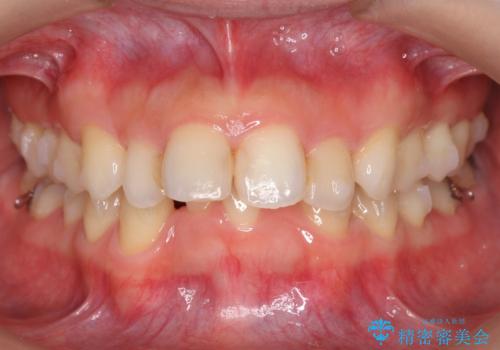

出っ歯 下の歯のガタガタ 下の前歯のみ1本抜歯 マウスピースで1年

- 出っ歯を主訴に来院。

航空会社勤務とのことで、矯正には会社の許可がいる上、許可を取るのが難しいだろうとのことでした。

育児休業中に矯正を終わらせることになりました。

下の前歯のがたつきがひどく、非抜歯では難しい状態でした。

古典的な方法では4本抜歯した後、ワイヤー矯正という方法も選択肢には上がりましたが、下の前歯を1本だけ抜くことにし、マウスピースで短期間で治療を終わらせるようにしました。

治療も比較的短期間で終わり、大変喜んでいただきました。

下の前歯を1本抜くと上下の正中はあいませんが、ほとんど目立ちません。